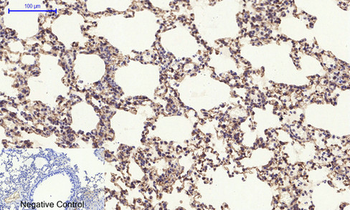

Immunohistochemical analysis of paraffin embedded mouse Alzheimer’s tissue labeling Tau with orb1294394 at 1/1000 RT 1hr. Epitope Retrieval methods: Citrate Buffer, pH 6.0.